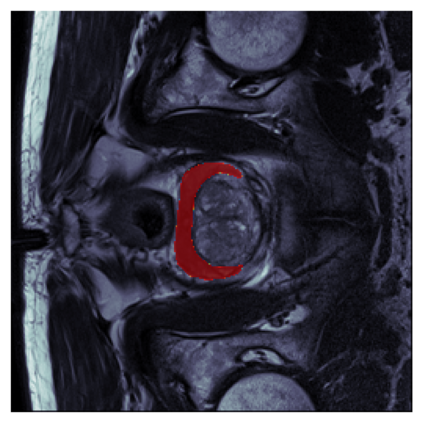

The sigmoid activation is the standard output activation function in binary classification and segmentation with neural networks. Still, there exist a variety of other potential output activation functions, which may lead to improved results in medical image segmentation. In this work, we consider how the asymptotic behavior of different output activation and loss functions affects the prediction probabilities and the corresponding segmentation errors. For cross entropy, we show that a faster rate of change of the activation function correlates with better predictions, while a slower rate of change can improve the calibration of probabilities. For dice loss, we found that the arctangent activation function is superior to the sigmoid function. Furthermore, we provide a test space for arbitrary output activation functions in the area of medical image segmentation. We tested seven activation functions in combination with three loss functions on four different medical image segmentation tasks to provide a classification of which function is best suited in this application scenario.